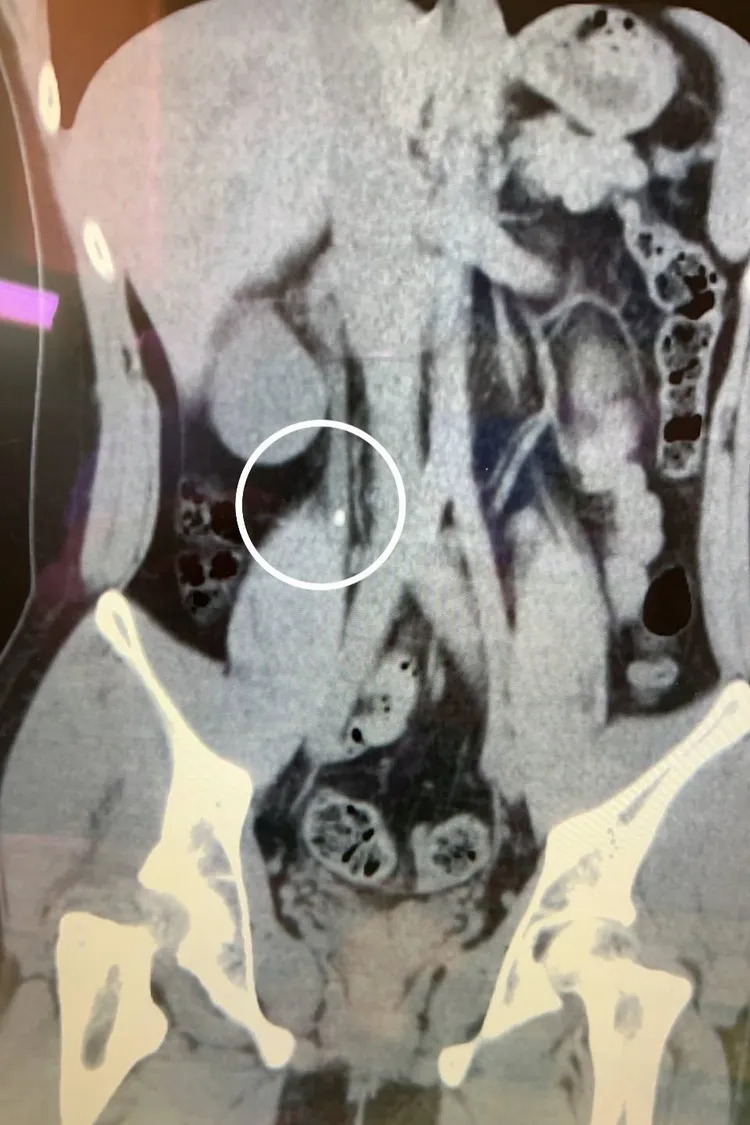

經過手術取出結石後,小周也恢復健康。阮綜合醫院提供